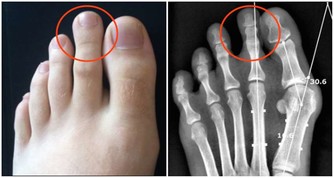

超聲科醫師檢查發現其右側陰囊空虛,右側腹股溝內可見大小約2*2*1cm的類睾丸迴聲,診斷考慮:隱睾症。

超聲科劉友員主任醫師解釋,“蛋蛋”不在陰囊裡就是俗稱的“隱睾症”。

隱睾,是指睾丸在正常發育過程中未下降或下降不全至陰囊,陰囊內沒有睾丸或只有一側有睾丸。

正常睾丸大小約4*3*2cm,位於陰囊內,

陰囊是最適合睾丸生長發育的場所,陰囊內溫度比體溫低1° C-2°C,有利於睾丸產生精子。

而隱睾患者睾丸未進入陰囊,長期留在腹腔和腹股溝管內,這些部分局部溫度高,

可導致睾丸生精細胞損害,影響精子的產生和生存,易導致不育。

此外隱睾由於生長環境改變以及發育上在障礙,容易發生惡變。

經綜合考慮,譚先生右側睾丸萎縮,失去了產生精子的能力,且存在惡變風險,於是醫生對其進行了單側隱睾切除術。